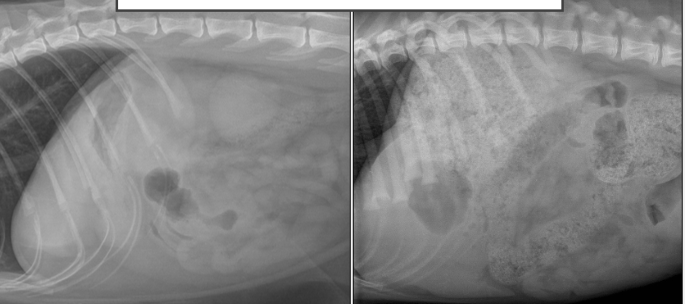

Complétez : La localisaiton du gaz varie selon la projection. En effet, le gaz gastrique sera déplacé en portion ______ dans les différentes zones gastriques selon le décubitus de l’animal.

non-déclive

Dire à quel endroit sera localisé le gaz gastrique pour chacun des décubitus suivant (*à connaitre) :

A) en décubitus latéral droit

B) en décubitus latéral gauche

C) en décubitus dorsal

D) en décubitus ventral

A) corps et fundus

B) l’antre/canal pylorique (pylore) et le duodénum

C) corps

D) fundus

=> gaz se retrouve en portion non-déclive